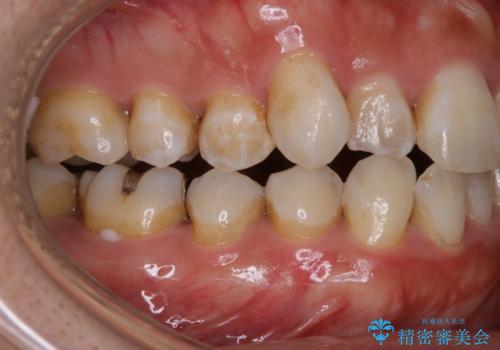

- ホワイトニングで、できる限り白くしたいとのことで来院されました。処置前クリーニング(¥3,300)・エクセレントホワイトニング(¥29,700)・トリートメント(¥550)を行いました。

ホワイトニング剤に含まれる過酸化水素・過酸化尿素には、歯を痛めることなく内部の色素を分解する力があります。ホワイトニング剤を塗布することで、より深いところの色素まで分解し、白くすることができます。